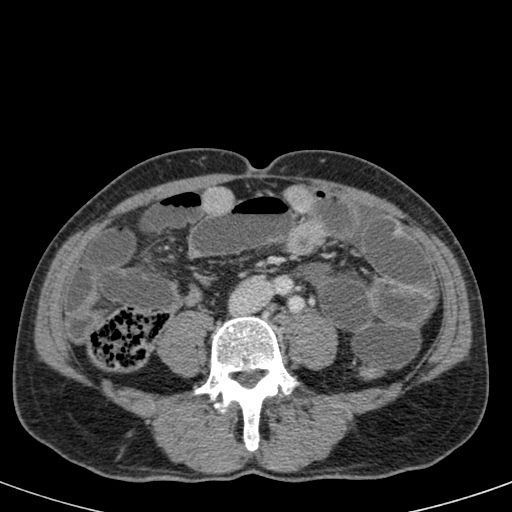

Nếu quai kín ngắn và nằm trong mặt phẳng tạo ảnh, chúng ta sẽ thấy quai ruột hình chữ U hoặc chữ C.

Tắc ruột dạng quai kín với các quai ruột giãn xếp theo hình nan hoa. Có dày thành ruột và phù nề mạc treo gợi ý thiếu máu cục bộ

Một hình ảnh quan trọng khác của tắc ruột dạng quai kín là các quai ruột non giãn xếp theo hình nan hoa với các mạch máu mạc treo hội tụ về một điểm trung tâm.

Hình ảnh này hầu như luôn do xoắn ruột non gây ra.

Các dấu hiệu thiếu máu cục bộ trong tắc ruột dạng quai kín tương tự như ở bệnh nhân thiếu máu mạc treo do các nguyên nhân khác:

- dày thành ruột

- phù nề mạc treo

- cổ trướng

- sự ngấm thuốc của thành ruột trong thiếu máu cục bộ có thể bình thường, tăng hoặc giảm.